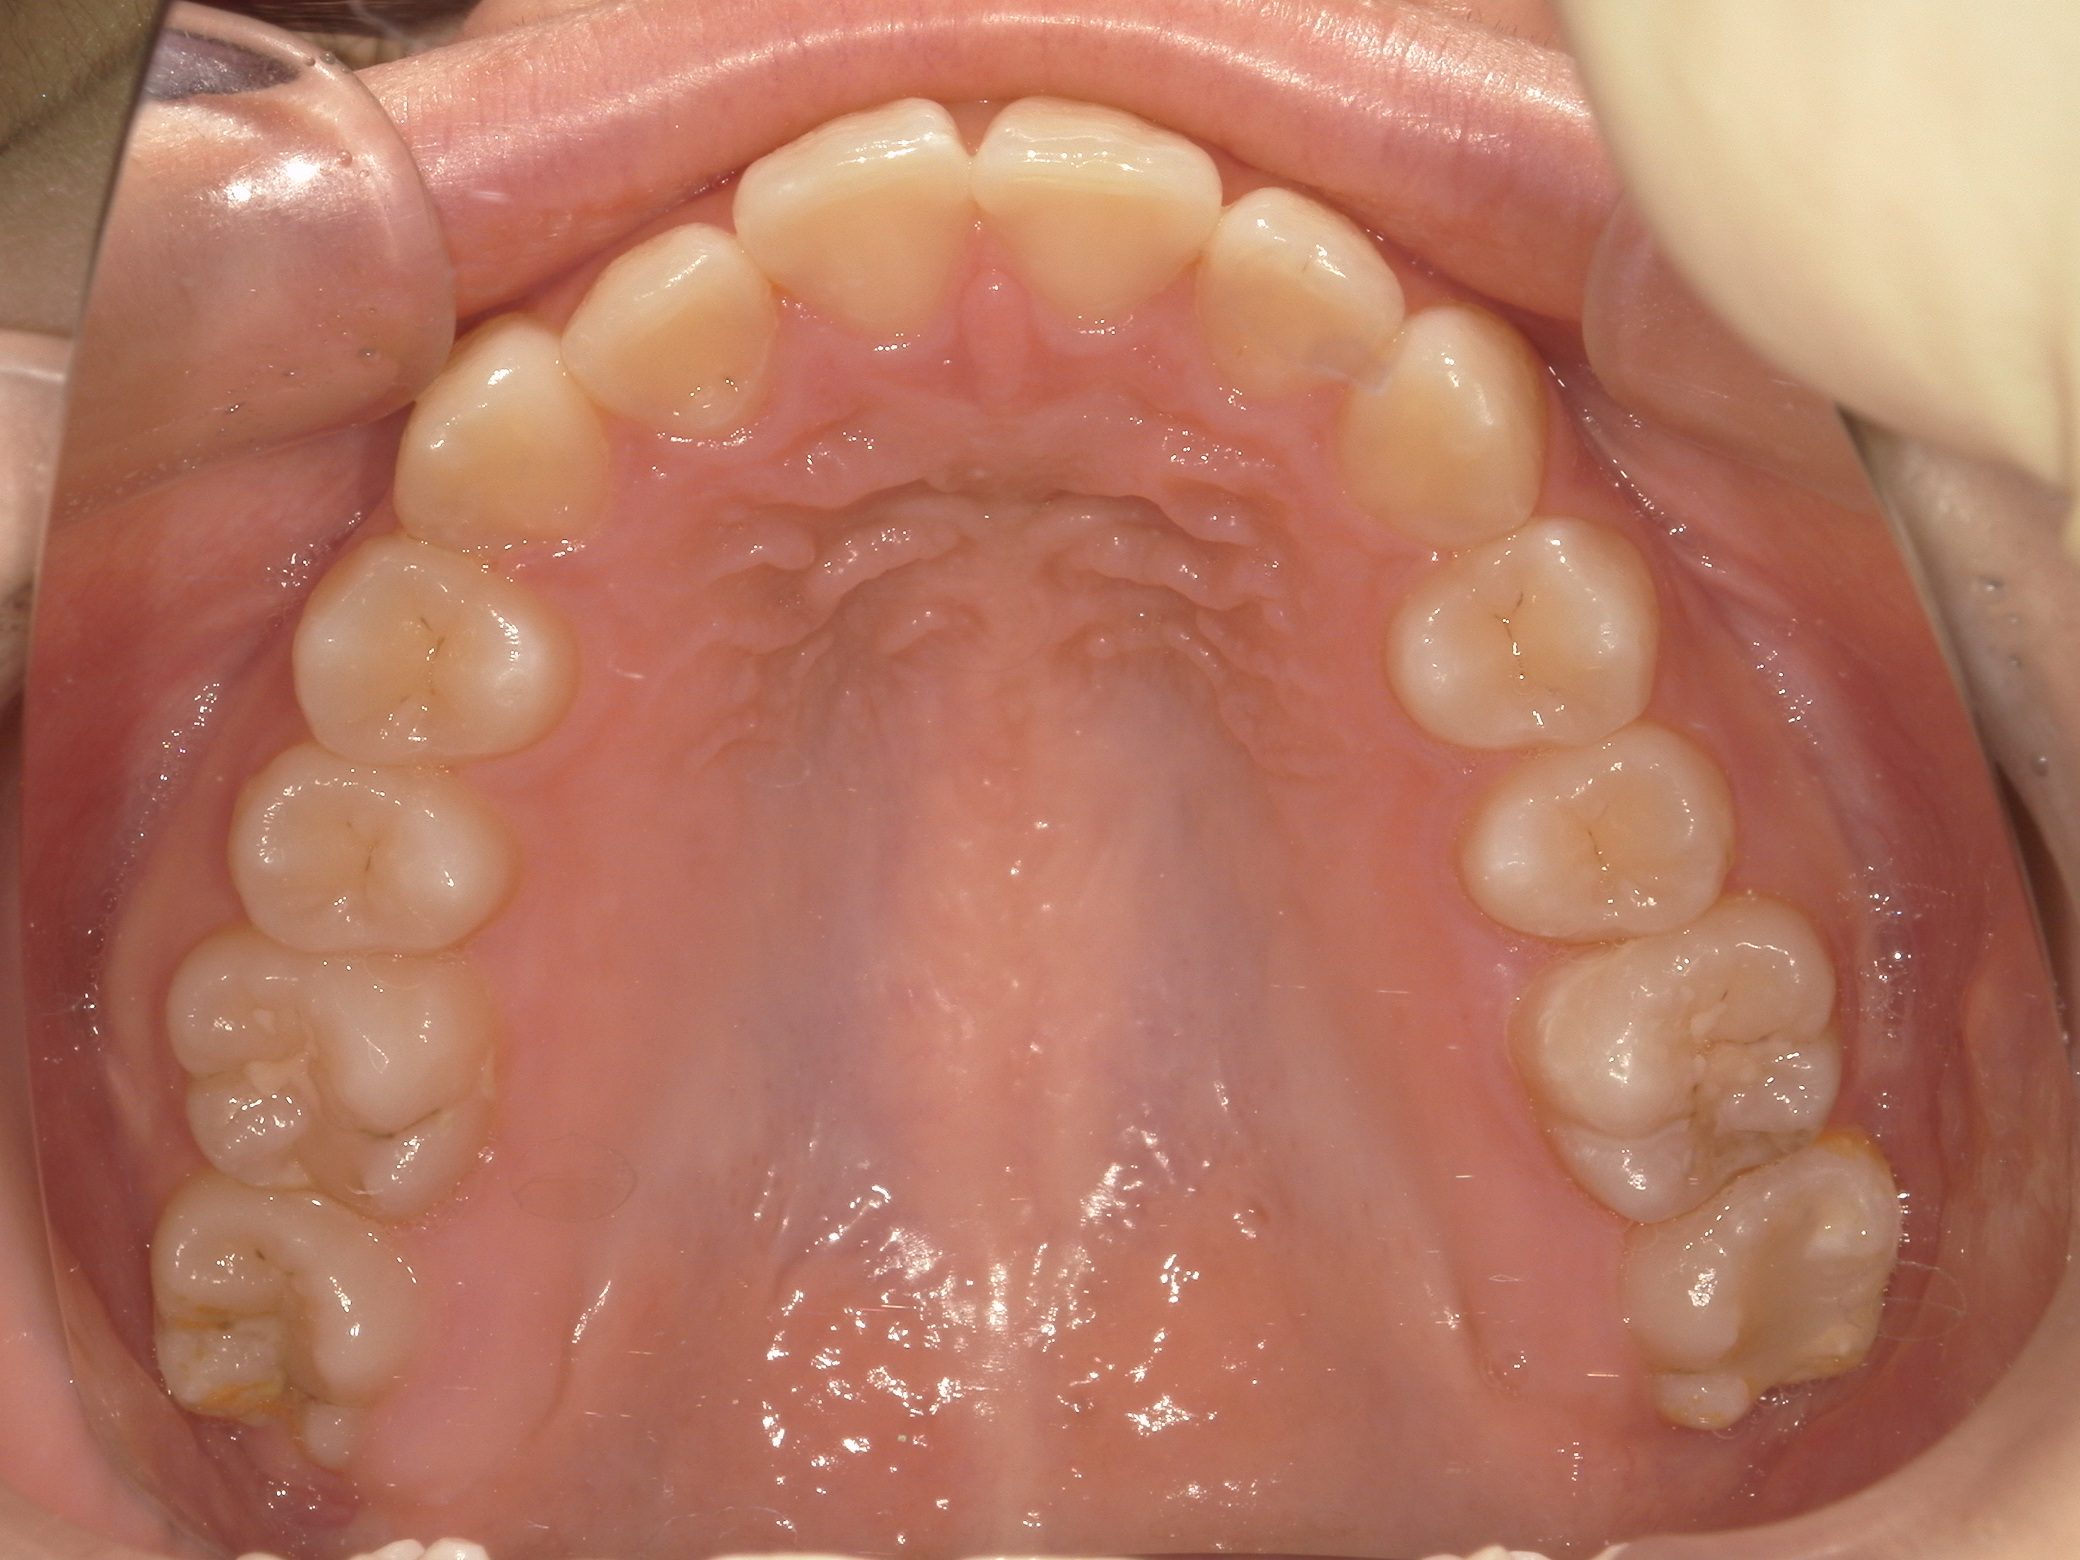

【小学生】 8歳 マイオブレース矯正 + インビザライン矯正 叢生(でこぼこ)を改善

Before

After

治療期間

3年年

治療開始

8歳

種類

マイオブレース矯正 + インビザライン矯正

使用装置

マイオブレース 3Dリンガルアーチ インビザライン

コメント

1期治療後 叢生(でこぼこ)が少し残ったので インビザラインで治しています

現在も 維持してくれています